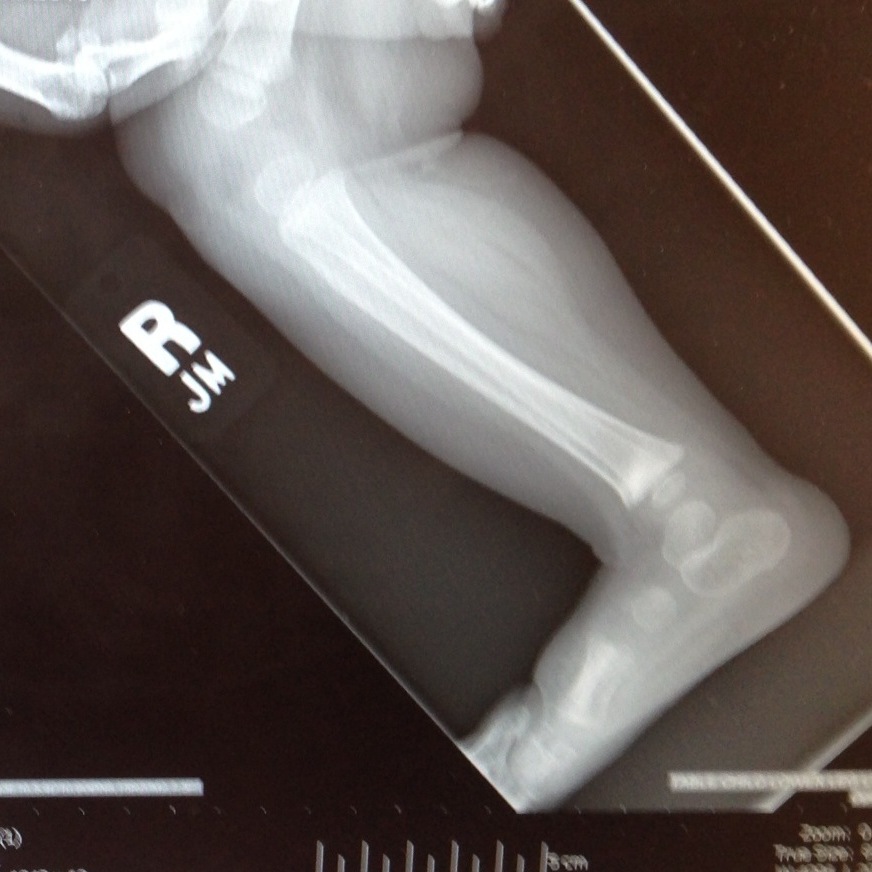

A few days later, our baby with a broken leg wanted to get up and walk. We tried hard for about 24 hours to keep her immobile, but FOR PETE’S SAKE, HAVE YOU EVER TRIED TO KEEP A ONE-YEAR OLD IMMOBILE? It was impossible. We decided to trust her, that she wouldn’t walk if it hurt, and we made an appointment to see a pediatric orthopedic surgeon when we got home, just to make sure her bone was healing properly. Due to some crazy circumstances, we didn’t get in to see the pediatriac surgeon until two weeks after the accident. He took new x-rays, and this is what he showed us:

Clara had, apparently, broken both of the bones in her lower right leg. The tibia and the fibula both had buckle fractures across the same line, probably a result of the way Sam held her tight against him when he fell. The surgeon said if he’d seen her after it happened, he would have cast her leg up to her hip, but it looked like her bones were healing perfectly even without any help, so he wasn’t going to give her a cast at all. It had only been two weeks, and her leg was almost completely healed. She hadn’t broken her growth plate (thank you Lord, that girl is already short enough) and he said she’ll be 100% in no time.

Whew! There you go, the long version of how these adorable x-rays came to be, and of our dramatic introduction to worrying about our children’s health and safety. But I mean seriously, have you ever seen an x-ray that is so damn cute?? Her leg chub, the miniature length of her calf… I melt.